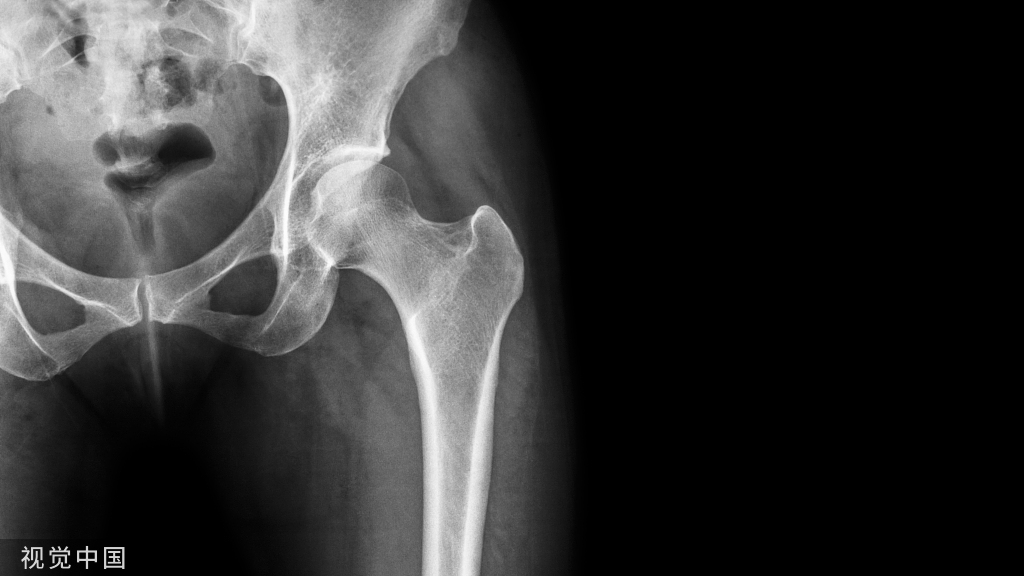

患者取侧卧位。患侧髋关节向上。患侧下肢屈曲20°。内收10°。健侧髋关节屈曲以减少脊柱前凸。手术开始前拍摄前后位x线片,确定骨盆位置。